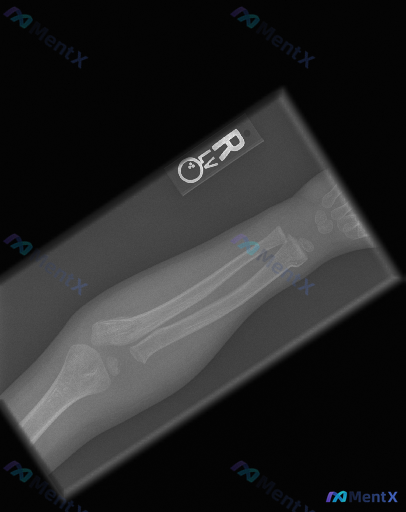

这张儿童右前臂正位X光片,最需要优先警惕的问题是什么?

- 患者:儿童/青少年(影像可见骨骺未闭合)

- 影像:右前臂正位X光片

- 骨骼:右侧桡骨和尺骨远端骨干可见完全性骨折,骨折端有重叠移位,骨折线横断或短斜型,断端移位明显,距离腕关节面较近;下尺桡关节解剖关系受破坏

- 软组织:骨折区域周围软组织影明显增宽、密度增高

- 骨质:未见明显骨质疏松或病理性破坏